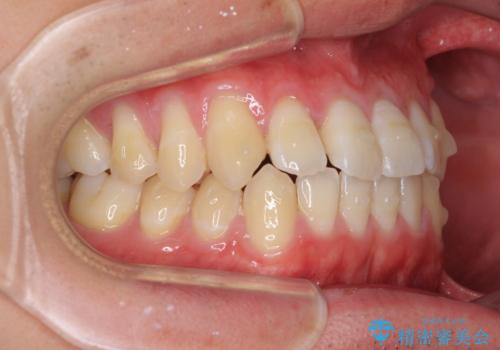

- 上下前歯のデコボコを気にして来院された患者様です。

叢生は軽微であり、費用を抑えて期間もあまりかけずに治療をしたいとのことで、インビザライン・ライトを用いて矯正治療を行うこととしました。

途中通院できなくなり、マウスピースの装着もしっかりとできなかったため、治療期間が長くかかってしまいました。